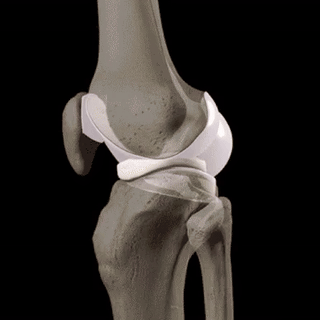

Osteoartrita distruge treptat țesutul cartilaginos și duce la deformarea articulațiilor. În timp, chiar și cele mai simple mișcări devin imposibile, iar durerea devine constantă. O terapie corectă ajută la încetinirea progresiei bolii.